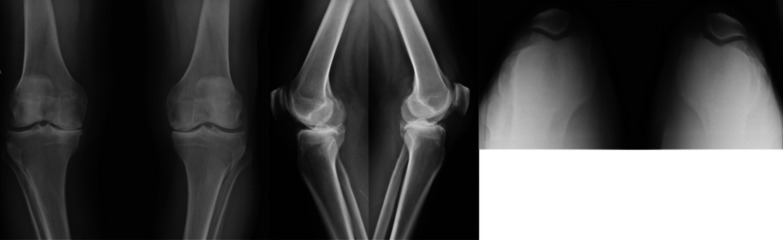

Background: Total knee arthroplasty (TKA) is the most effective treatment for end-stage adult knee osteoarthritis, but it has been reported that patient satisfaction may vary. A malfunction of the patellofemoral joint may produce anterior knee pain (AKP) for several reasons. While some surgeons systematically resurface the patella despite the risk of potential complications such as fracture, loosening, or wear of the patella, others prefer to preserve it to reduce AKP and revision rates. This study aimed to evaluate whether patellar resurfacing had better clinical and functional outcomes, complications, and revision rates in patients undergoing simultaneous bilateral total knee arthroplasty.

Methods: We conducted a prospective cohort study, including patients who underwent bilateral simultaneous TKA in which the patella was replaced in one knee and preserved in the other, with a minimum follow-up of 7 years. We assessed clinical and functional outcomes with the Knee Society Score (KSS) and Visual Analogue Scale (VAS); complications and revision rates were also registered.

Results: The final series consisted of 43 patients with 86 knee arthroplasties. After a mean of 7.6 years of follow-up, no significant differences were found regarding KSS (clinical: 82.8 ± 7.4 versus 83.2 ± 3.4, p = 0.92; functional 89.1 ± 8.2: versus 90.4 ± 6.8; p = 0.99), VAS (2.0 ± 0.9 versus 1.8 ± 1.0; p = 0.84), complications (10.5% versus 8.1%; p = 0.57), or revision rates (2.3% versus 2.3%; p = 0.99) when comparing patellar resurfacing versus retention.

Conclusion: In the context of total knee arthroplasty, patellar replacement did not demonstrate statistically significant differences concerning patellar retention in clinical nor functional outcomes, AKP, complications, or revision rates after a minimum of 7 years of follow-up.